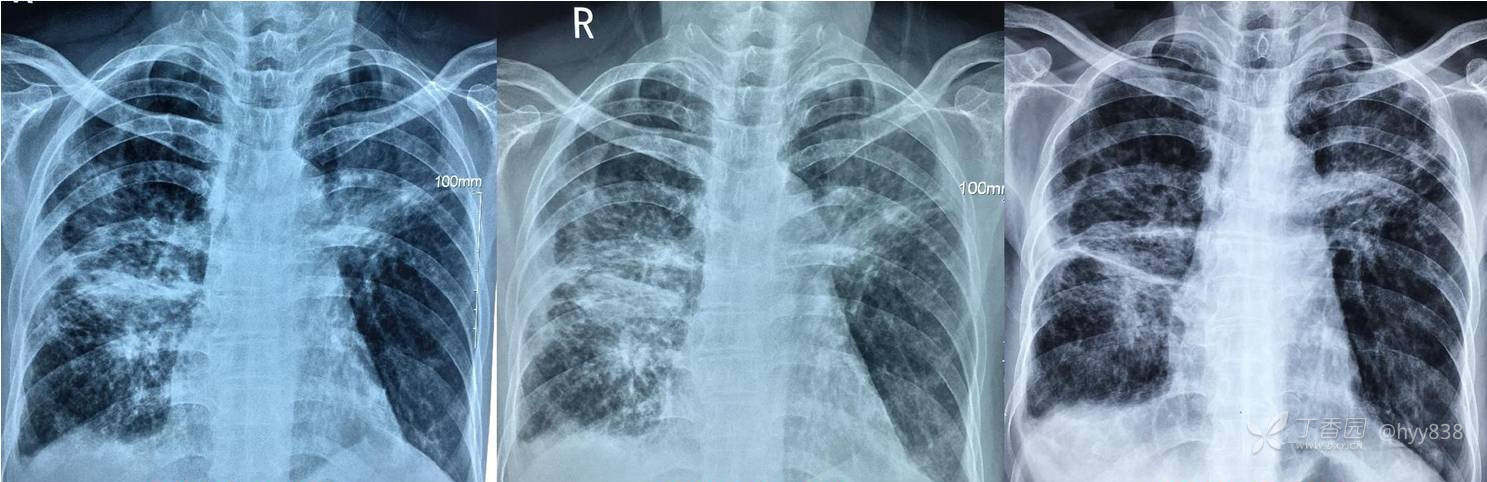

第一次胸部CT

上半年抗痨治疗连续三个月复查

中间停药,下半年继续抗痨治疗

次年行CT复查,病灶进展